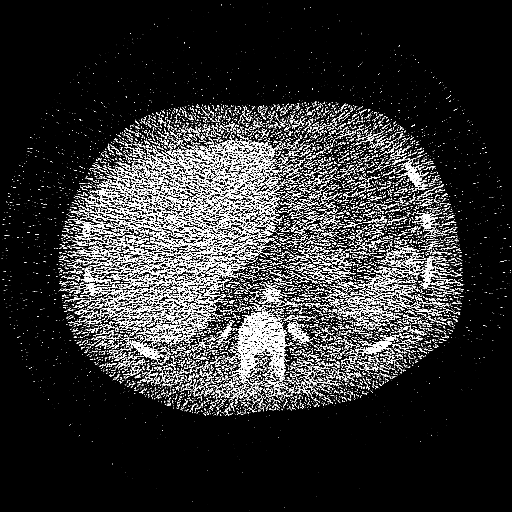

(digital human)